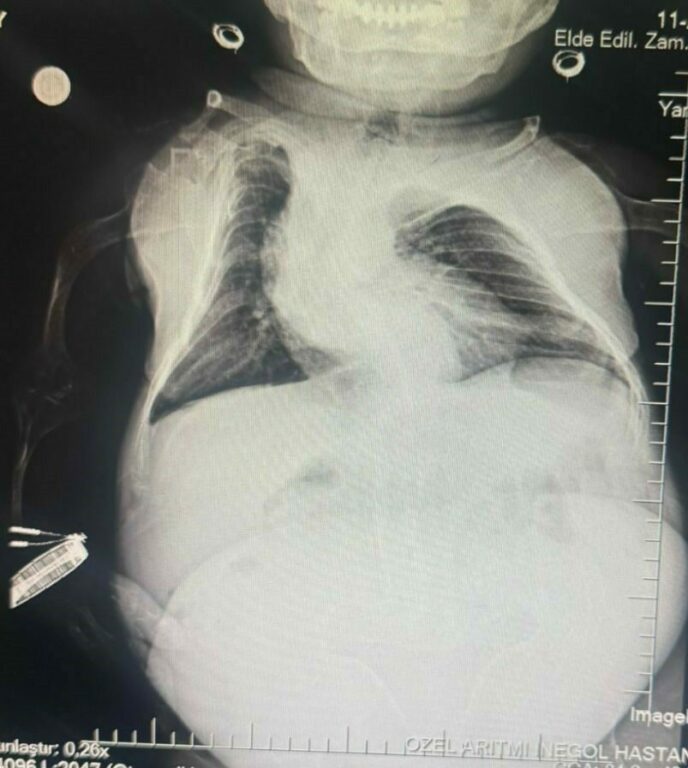

Anestezi Doktoru Mahmut Gül, “Hastamız 30 yaşında. 80 santimetre boyunda, 24 kilo ağırlığında bir kardeşimiz. Kendisinin yumurtalıklarında kist olduğu için ameliyat olması gerekti. Biz bu ameliyatta hastamıza önce büyük bir damar yolu açtık kasıktan. Çünkü damar yolunun çok önemi var ve daha sonrasında ameliyat sırasında belinden uyuşturduk ve ameliyatı sorunsuz bir şekilde belden uyuşturmayla hastamız uyanık bir şekilde tamamladık. Hastadan 3 kilo kist çıktı. Öncesinde 24 kilo olan hastamız, ameliyat sonrasında 21 kiloyla şifalı bir şekilde serviste yatıyor. Ameliyatı bugün oldu. Şu anda da serviste hastamız. Bu tür ameliyatlarda uyutmak hastamız açısından oldukça risklidir. Biz o yüzden bölgesel anesteziyi yani belden uyuşturmayı tercih ettik. Literatürde çok olmayan bir hasta ve güvenli bir şekilde hastanemizde bu ameliyat tamamlandı” dedi.

Kadın Hastalıkları Uzmanı Mustafa Kır, “Hastamızda 20 santimlik tümör vardı kistlik yapıda. Onu başarılı bir operasyonla çıkarttık” şeklinde konuştu.